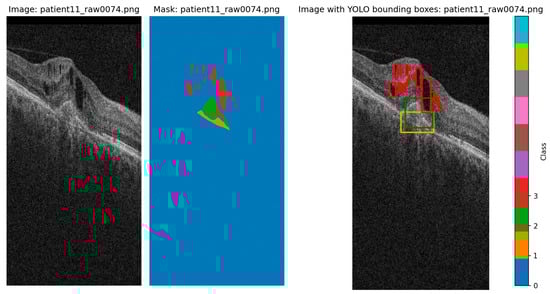

2.5. Data

2.5.1. AROI Dataset

2.5.2. OCT5k Dataset

3.1. Performance Analysis of YOLO Versions on the AROI Dataset